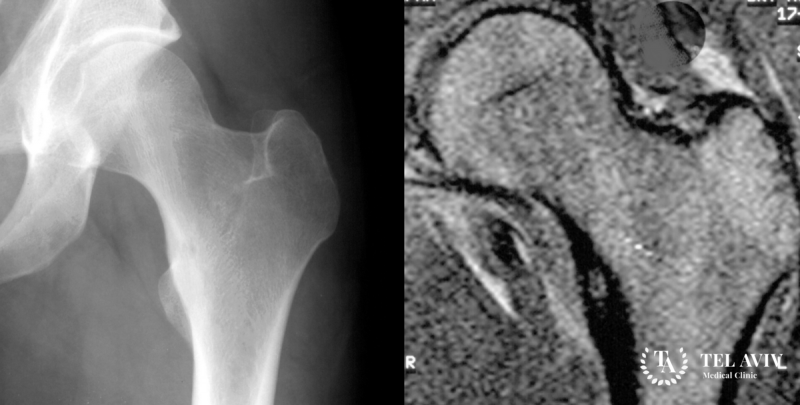

Гигантоклеточная опухоль кости (остеобластокластома, остеокластома) – это доброкачественная опухоль костной ткани, которая склонна к местно-деструктивному течению, то есть новообразование по […]